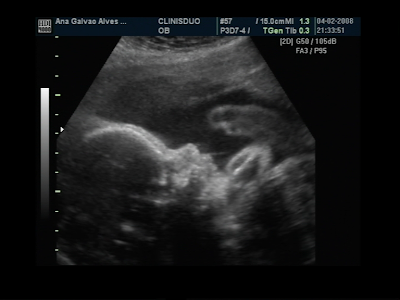

Fizemos um video com partes da última ecografia para partilhar convosco.

Espero que gostem!

Com 27 semanas (a 1 semana dos 7 meses) o Francisco tem 1 quilito.

Na última Eco tinha 430grs que foi há 1 mês e meio aproximadamente.

Está no percentil 50 o que quer dizer que é um bebé médio, está exactamente com o peso certo nem acima, nem abaixo da média, um rapaz equilibrado!

Está lindo! já está mesmo com carinha de bebé! Adorei vê-lo!

Para quem já tem saudades de o ver deixo umas fotos da última visita ao médico.